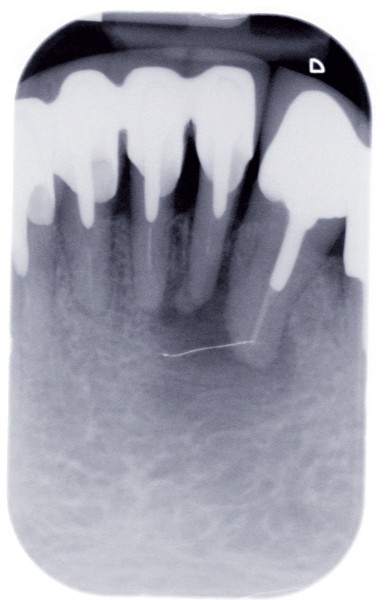

Le contrôle radiologique rétro-alvéolaire montre, quant à lui, une parfaite préservation de l’ostéointégration à 6 ans(fig. 3a et b).

Cette ostéointégration est confirmée par le Cone Beam(fig. 4a et b).